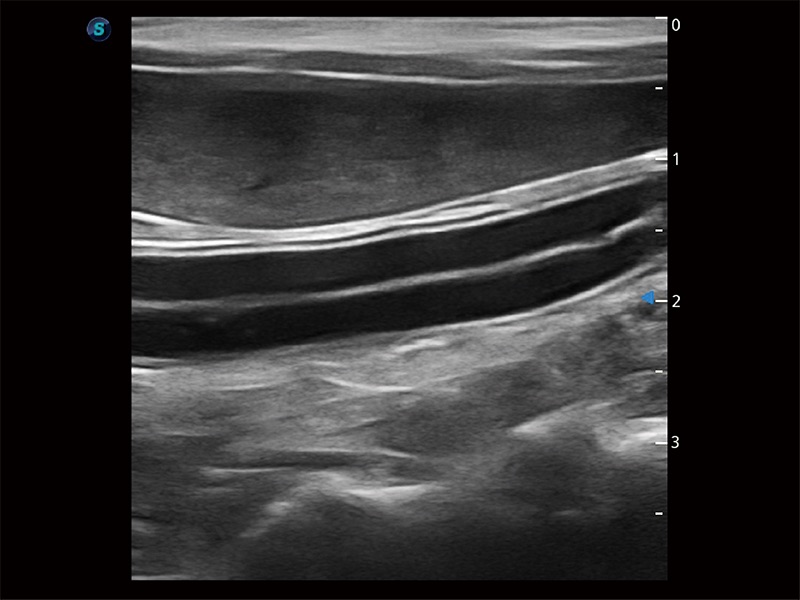

高性能和先進的臨床應用工具可以為動物醫(yī)生提供臨床信心。ProPet 80 搭載了先進的腹部和淺表應用工具,幫助醫(yī)生在日常臨床實踐中發(fā)揮前所未有的作用。

極大提升超低速微細血流的檢出能力,同時更精準地濾除軟組織和超聲信號,為獸用醫(yī)生提供以往無法通過常規(guī)血流獲得的疾病診斷信息。

在傳統(tǒng)二維血流成像的基礎上,呈現(xiàn)血流的立體感,具有動感的生命力之美。即便是微小的血管也能輕松應對,提高了血流的視覺敏感性。

操作簡便,無需高頻度外力作用即可真實反映組織的形變,快速評估腫瘤良惡性。